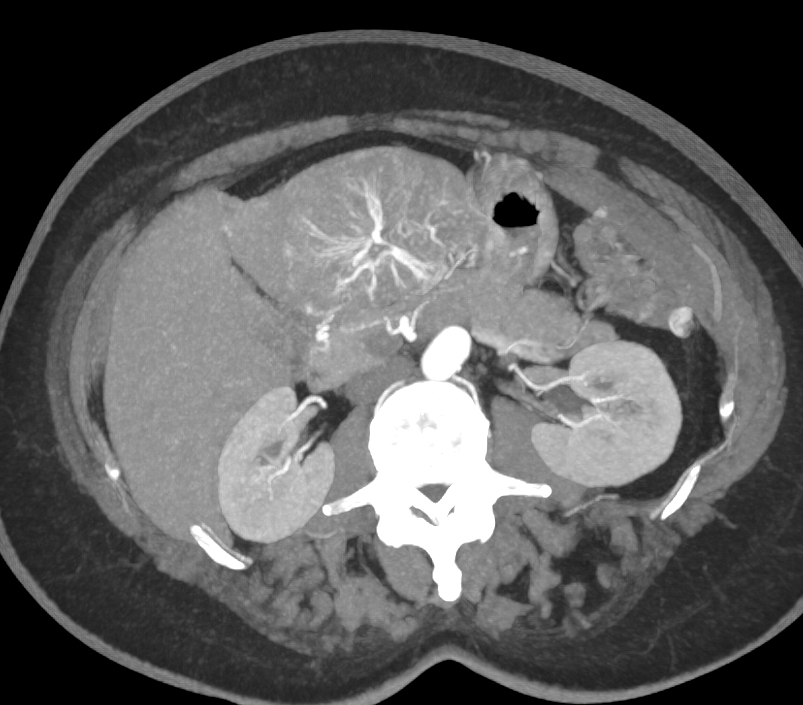

Diagnostic Case Quiz ❯ Anatomical Region Quiz: Liver

The most likely dx in this case is?

hepatic adenoma

focal nodular hyperplasia

hepatoma

hemangioma